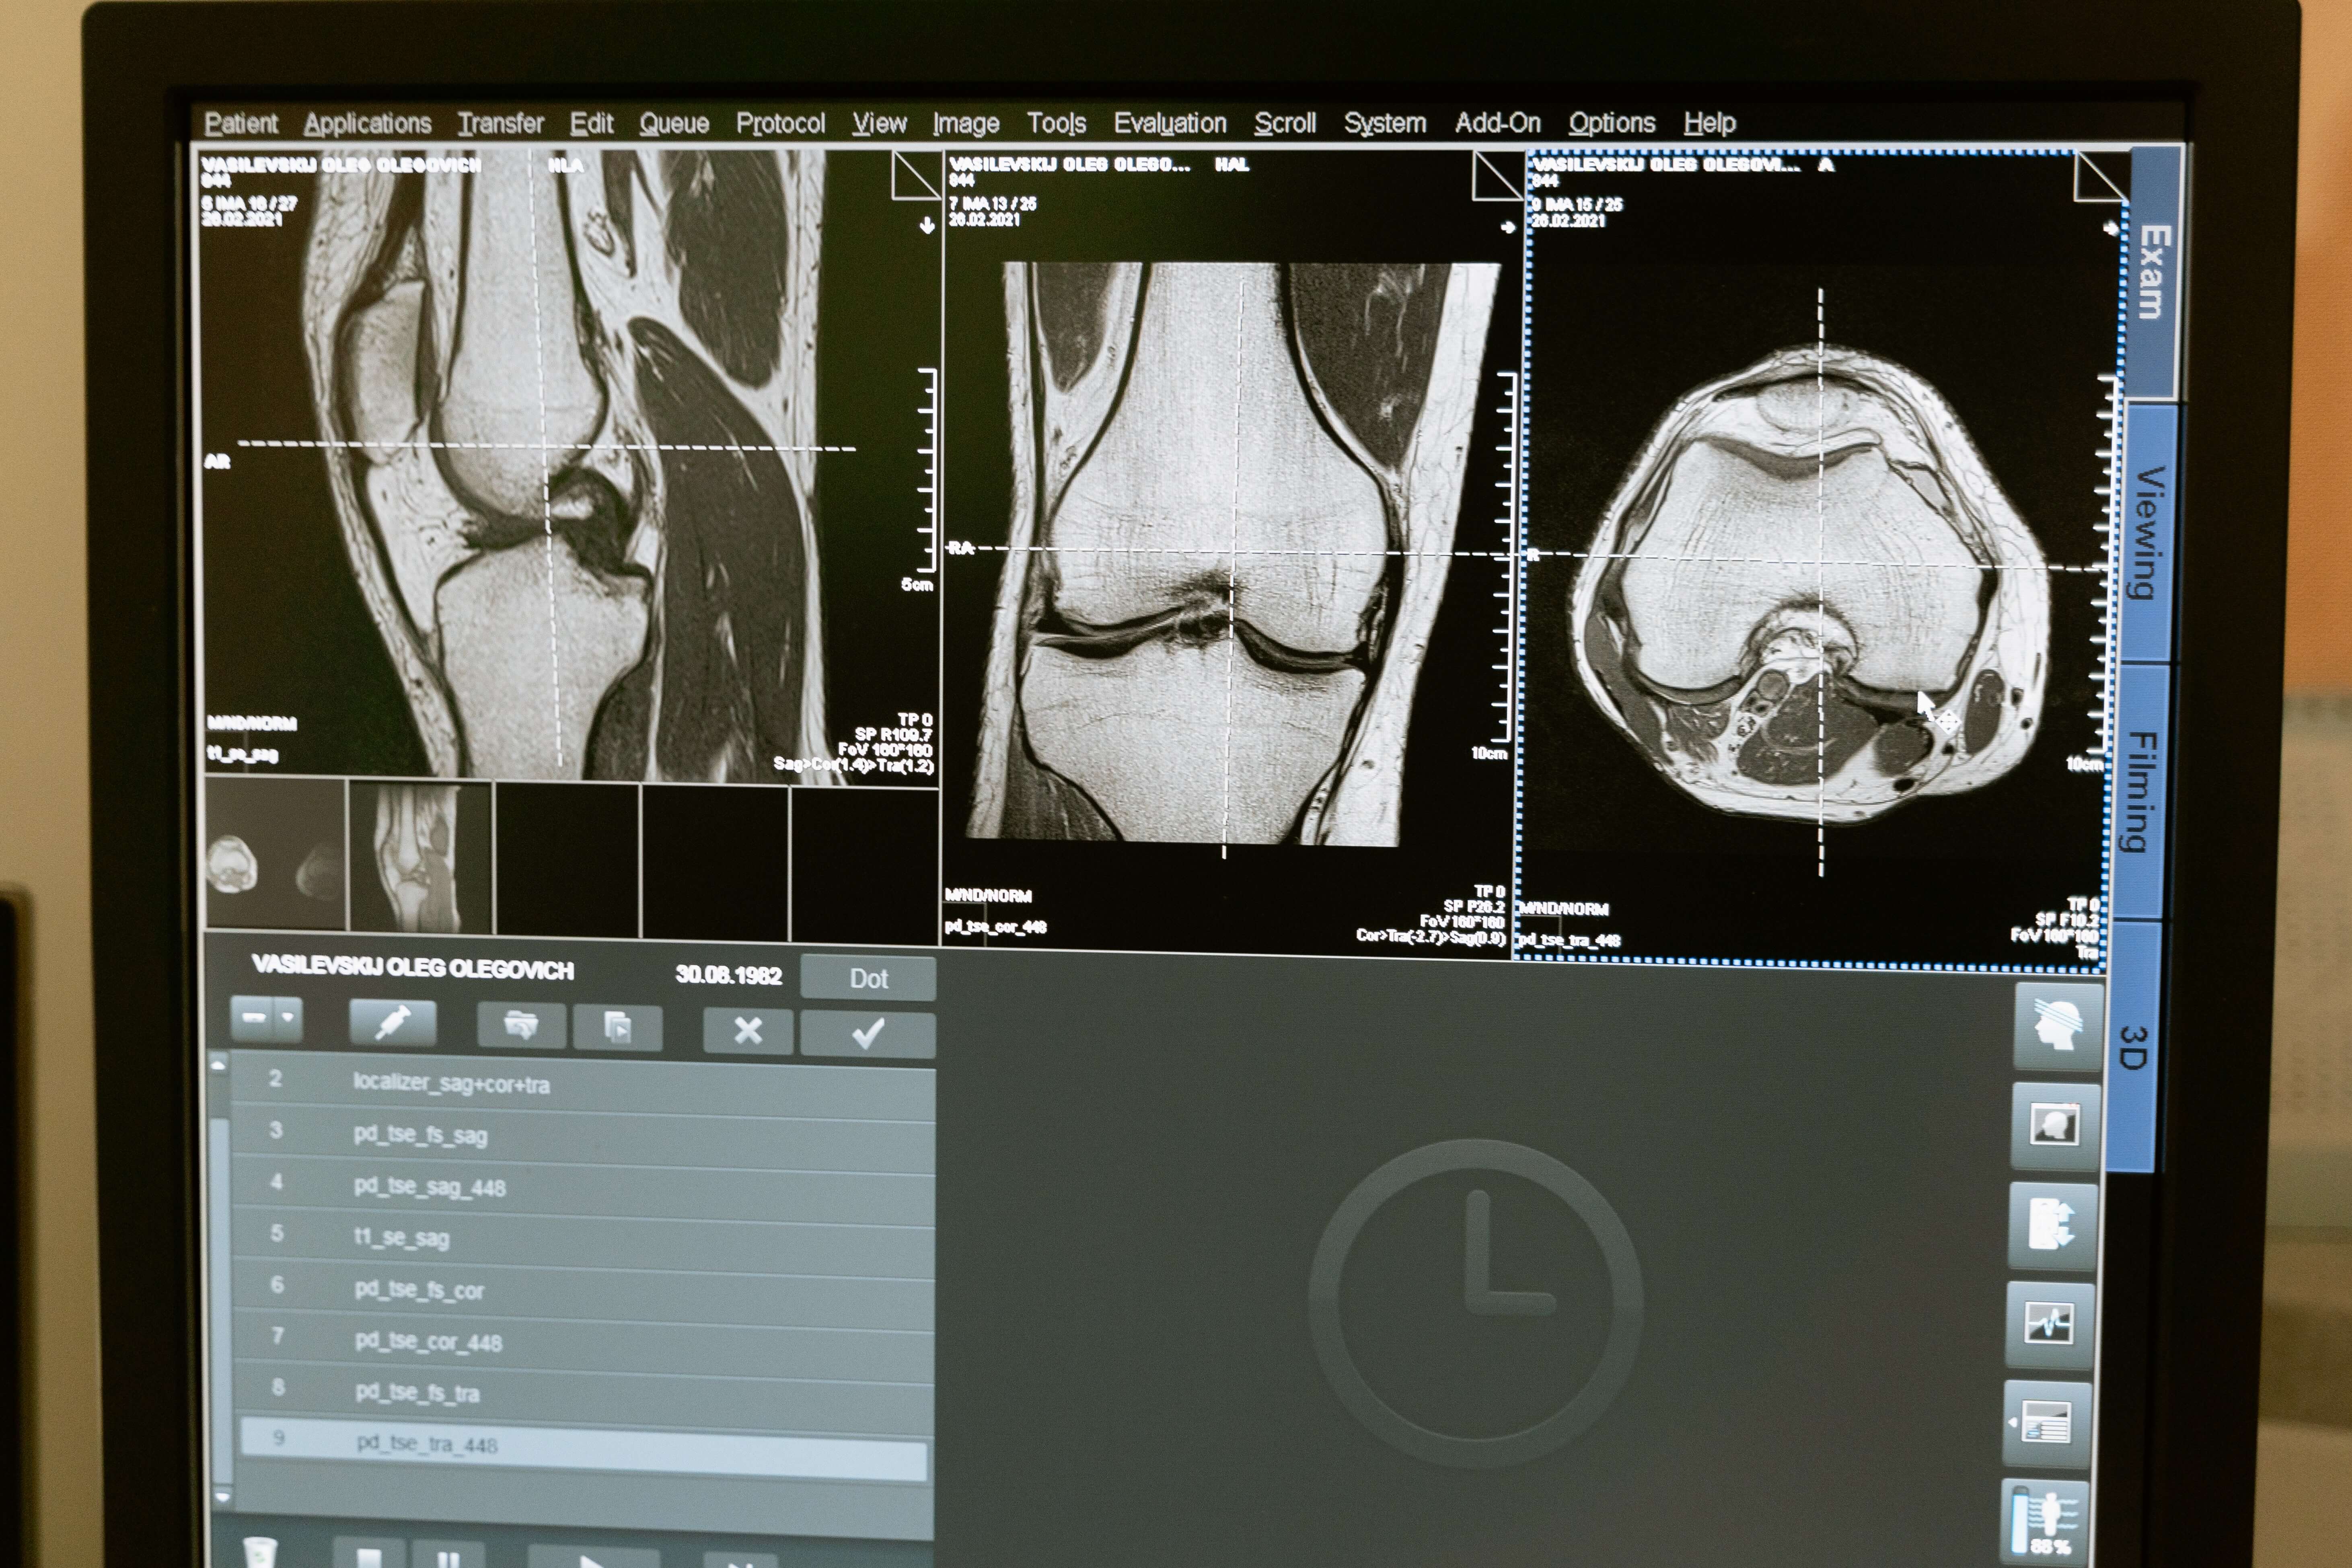

관절염 이란 관절이란 두 뼈가 맞닿아서 운동이 이루어지는 곳인데, 퇴행성관절염이란 물렁뼈가 닳아지면서 병이 진행되고 결국에는 부분적으로 물렁뼈가 아주 벗겨져 버리는 병이고, 류마티스관절염은 관절을 싸고 있는 활막에 염증이 생기고 점차 심해져서 이차적으로 물렁뼈가 파괴되는 병입니다.

2. 관절염의 증상

(1) 관절에 염증이 생기며 관절이 빨갛게 부어 오르며,

(2) 그 부위에 압박을 주면 통증을 느끼고,

(3) 심한 경우에는 건드리지 않아도 통증을 느끼며,

(4) 관절을 움직이기에 힘이 들며,

(5) 관절의 변형과 불구가 오게 됩니다.